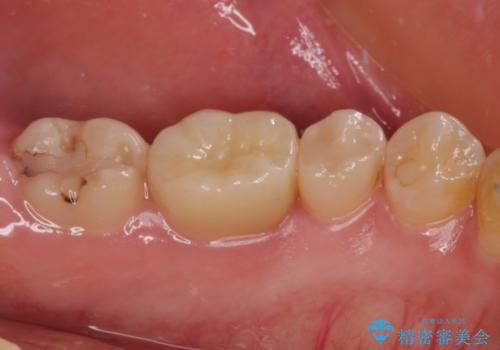

- 今まで色々と修復を重ね、いよいよものが挟まるとのことで来院された患者様です。

ものが挟まるだけであれば、インレーによる修復治療を選択しますが、今までの治療後が黒く汚く見えるとのことで、オールセラミッククラウンにて補綴治療を行うこととしました。